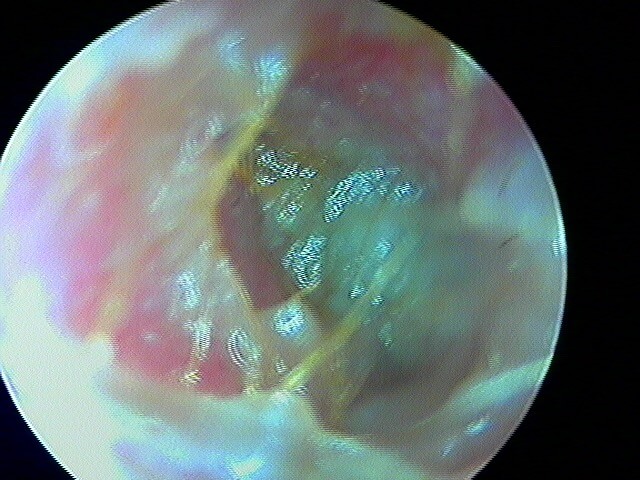

3/2 barotraumatique

– stade I : hyperhémie du manche du marteau et de la pars flaccida ;

– stade II : tympan rétracté, congestif, immobile

– stade III : aspect d'otite séromuqueuse

– stade IV : aspect otite séro-hémorragique, otohématome

– stade V : perforation

Ici des stades V perforés